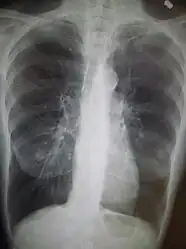

A chest X-ray and complete blood count may be useful to exclude other conditions at the time of diagnosis.[82] Characteristic signs on X-ray are hyperinflated lungs, a flattened diaphragm, increased retrosternal airspace, and bullae, while it can help exclude other lung diseases, such as pneumonia, pulmonary edema, or a pneumothorax.[83] A high-resolution CT scan of the chest may show the distribution of emphysema throughout the lungs and can also be useful to exclude other lung diseases.[25] Unless surgery is planned, however, this rarely affects management.[25] A saber-sheath trachea deformity may also be present.[84] An analysis of arterial blood is used to determine the need for oxygen; this is recommended in those with an FEV1 less than 35% predicted, those with a peripheral oxygen saturation less than 92%, and those with symptoms of congestive heart failure.[24] In areas of the world where alpha-1 antitrypsin deficiency is common, people with COPD (particularly those below the age of 45 and with emphysema affecting the lower parts of the lungs) should be considered for testing.[24]

Chest X-ray demonstrating severe COPD: Note the small heart size in comparison to the lungs.